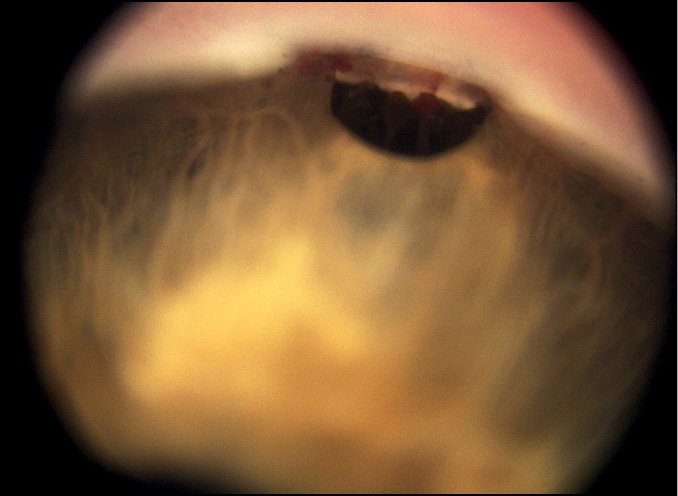

Анализ гониоскопического состояния области ВФ — области склерэктомического окна, иссечённого при ТЭ — показал (табл. 1), что среди вариантов заращения ВФ преобладал частичный блок ВФ (75,3%) (рис. 1), а полный блок ВФ наблюдался только в четверти случаев (24,7%) (рис. 2).

Рис. 1. Частичный блок внутренней фистулы.

Рис. 2. Полный блок внутренней фистулы.